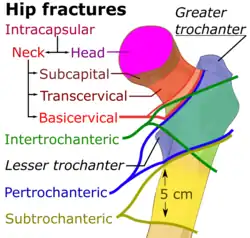

| Types | Intracapsular, extracapsular (intertrochanteric, subtrochanteric, greater trochanteric, lesser trochanteric)[1] |

Types

X-rays of the affected hip usually make the diagnosis obvious; AP (anteroposterior) and lateral views should be obtained.

| Capsule | Area | Classification | ||

|---|---|---|---|---|

| Intracapsular | femoral head | AO 31-C1 – 31-C3 | Pipkin classification | |

| femoral neck | Subcapital | AO 31-B1 – 31-B3 | Garden classification, Pauwel's classification | |

| Transcervical | ||||

| Basicervical | ||||

| Extracapsular | Trochanteric | Intertrochanteric (between the greater and lesser trochanter[18]) | AO 31-A1 – 31-A2 | Evans' classification (1949), Ramadier's classification (1956), Boyd and Griffin's classification (1949), Decoulx & Lavarde's classification (1969), Ender's classification (1970), Tronzo's classification (1973), Evans-Jensen classification (1975), Deburge's classification (1976), Briot's classification (1980) |

| Pertrochanteric (through the trochanters[18][19]) | AO 31-A3 | |||

| Subtrochanteric | AO 32 | Seinsheimer classification | ||

Trochanteric fractures are subdivided into either intertrochanteric (between the greater and lesser trochanter[18]) or pertrochanteric (through the trochanters[18][19]) by the Müller AO Classification of fractures.[20] Practically, the difference between these types is minor. The terms are often used synonymously.[21][22] An isolated trochanteric fracture involves one of the trochanters without going through the anatomical axis of the femur, and may occur in young individuals due to forceful muscle contraction.[23] Yet, an isolated trochanteric fracture may not be regarded as a true hip fracture because it is not cross-sectional.